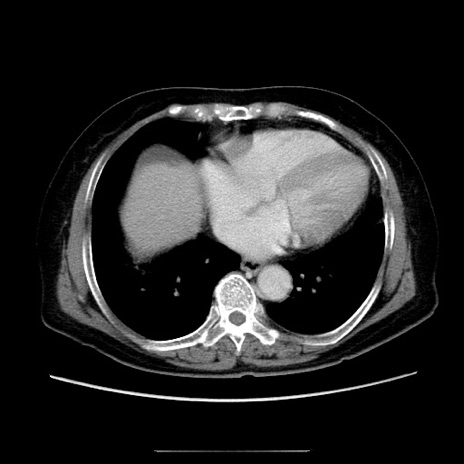

冠状断像